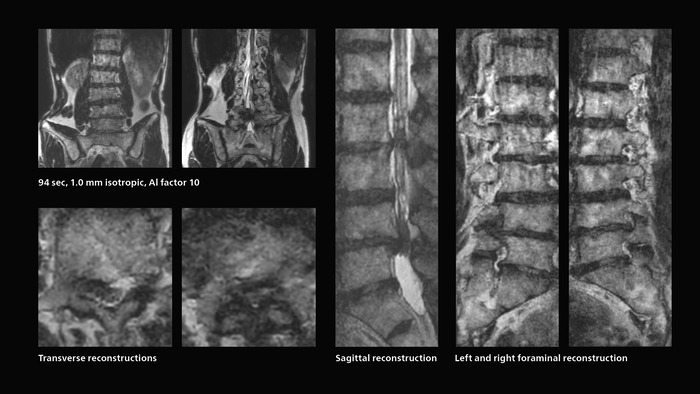

Many patients who must undergo a lumbar spine examination suffer from back pain. For these patients it is difficult to maintain the imaging position long enough to successfully complete the examination. “In such cases, using SmartSpeed allows us to perform volume imaging, so that we acquire only one high resolution 3D sequence in a short time and then reconstruct the other orientations from that,” Dr. Katahira says. “This is highly advantageous because the patient needs only endure a short exam time, whereas before it was necessary to acquire a larger number of sequences in total. We have seen that the shorter time has allowed us to scan patients who previously could not finish the exam. This is a great advantage.”

A patient arrived saying that undergoing MRI was not possible because of severe back pain and leg pain, was imaged with SmartSpeed in only 94 seconds. The scan was diagnostic and afterwards the patient confirmed that it only took a little while. Performed on Elition X.

The hospital’s fast lumbar spine ExamCard includes T2W SpineVIEW, 1:40 min, 1.0 mm isotropic, acceleration factor 12.